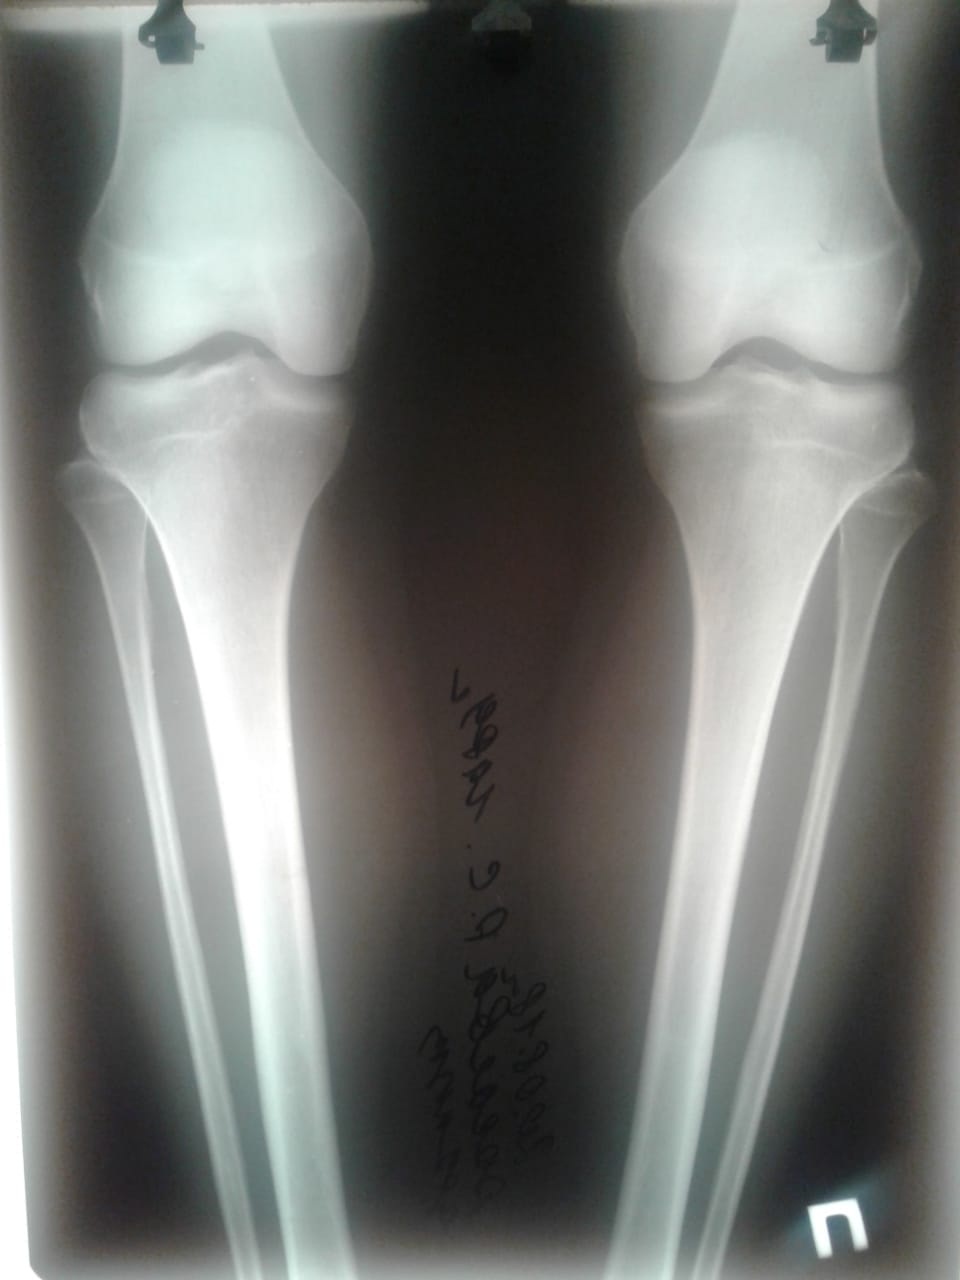

Исходник - 29 лет.

Дата операции - 23.08.2018г.

Ротация справа.

Ножки на сегодня.

Дата снятия аппаратов-29.11.2018г.

Срок сращения- 95 дней.